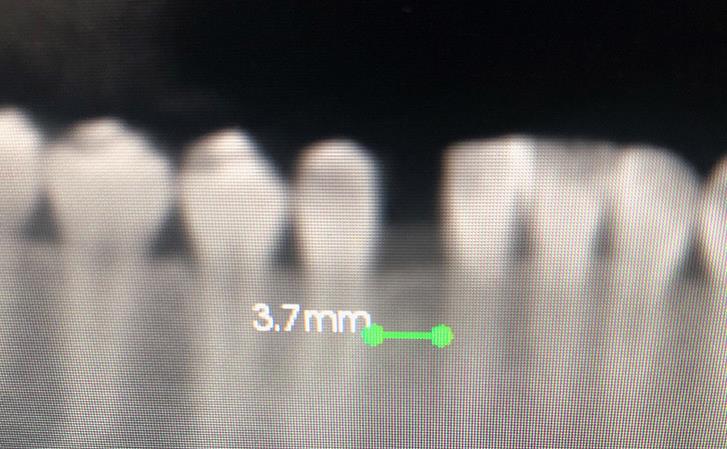

Patient presented with missing lower from tooth. The amount of space available to place an implant was very limited and posed a risk to injure the roots of adjacent teeth. This case was performed under guided surgery to assure perfect placement of the implant without injury to adjacent teeth.